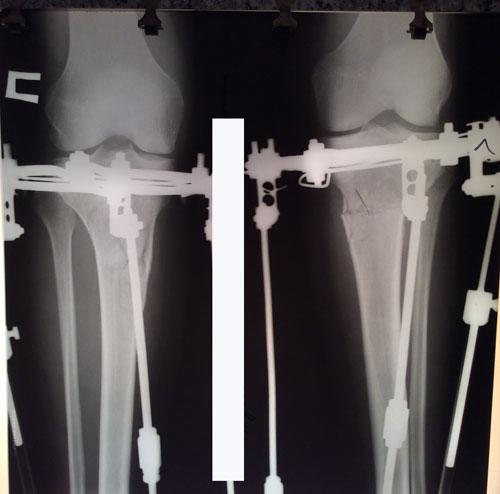

Рентген на фиксации.

Ножки на сращении

Дата операции - 18.01.2017г.

Дата снятия аппаратов 04.04.2017г.

Срок лечения - 75 дней.